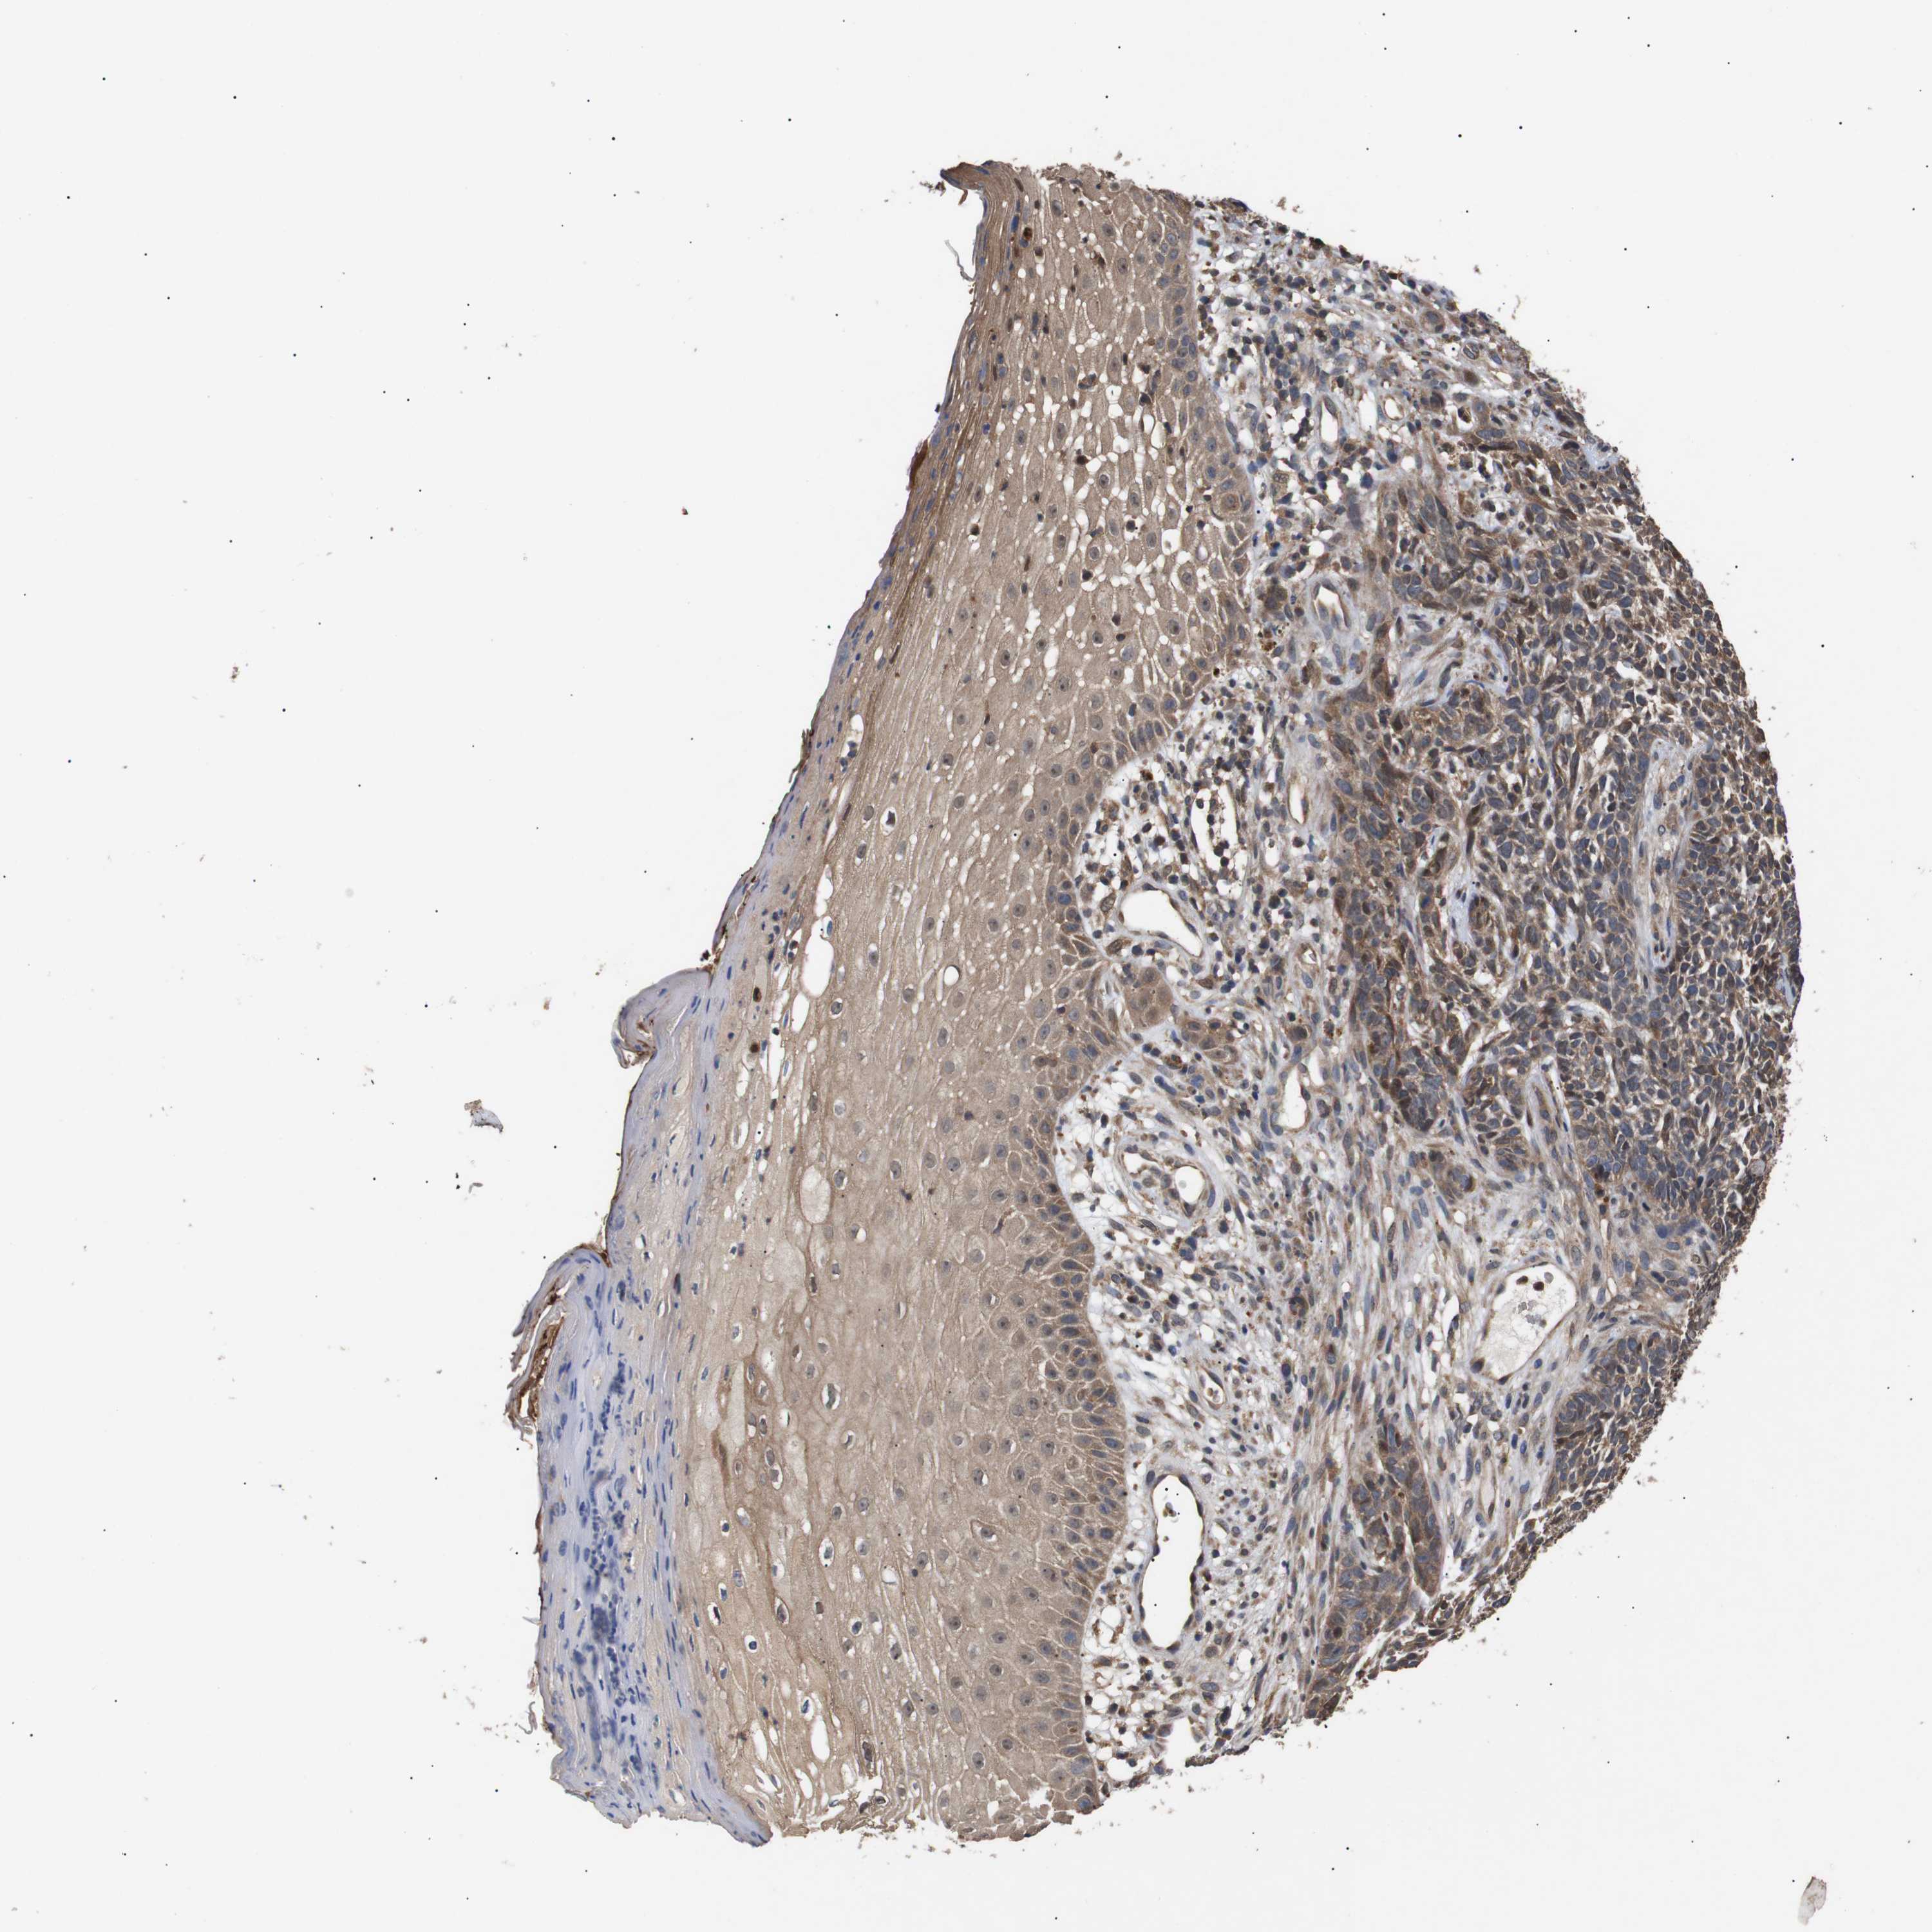

Basal cell and squamous cell cancer

SKIN CANCER - Protein expressioni

A mouse-over function shows sample information and annotation data. Click on an image to view it in a full screen mode. Samples can be filtered based on level of antibody staining by selecting one or several of the following categories: high, medium, low and not detected. The assay and annotation is described here.

Antibody stainingi

Antibody staining in the annotated cell types in the current human tissue is reported as not detected, low, medium, or high, based on conventional immunohistochemistry profiling in selected tissues. This score is based on the combination of the staining intensity and fraction of stained cells.

Each image is clickable and will lead to virtual microscopy that enables deeper exploration of all samples and also displays staining intensity scores, fraction scores and subcellular localization as well as patient and tissue information for each sample.

Antibody CAB010162

Antibody CAB025656

Staining

High

Medium

Low

Not detected

Intensity

Strong

Moderate

Weak

Negative

Quantity

>75%

75%-25%

<25%

None

Location

Nuclear

Cytoplasmic/membranous

Cytoplasmic/membranous,nuclear

Squamous cell carcinoma, NOS

Basal cell carcinoma

Squamous cell carcinoma, metastatic, NOS